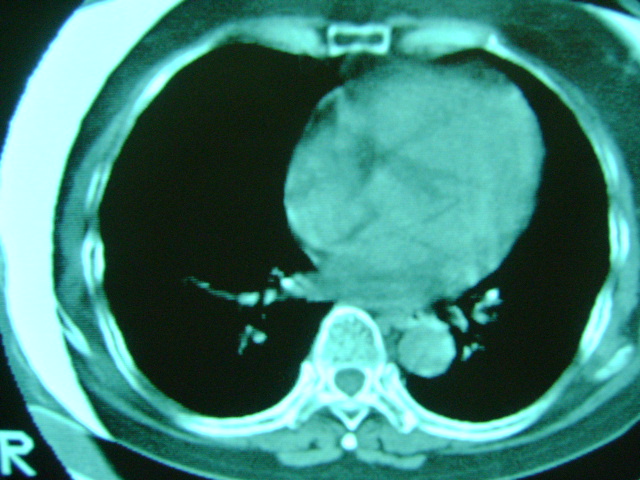

朋友的母亲,56y,咳嗽三个月,感觉左肺门不对,请大家给点意见

左肺门未见异常‘右肺有少许感染,图象质量不好